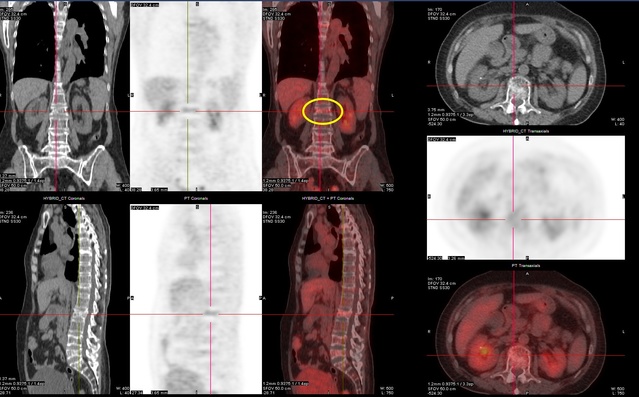

台中53歲楊姓女子去年彎腰取物時,突然「啵」一聲,頓時上背劇痛、上半身無法旋轉,右側痛到肩膀無法上舉,四處求醫仍未好轉,之後陸續出現下背痛及坐骨神經痛,讓她苦不堪言,直到安排抽血及骨髓穿刺,確診罹患多發性骨髓瘤,採標靶治療合併放射線治療後,癌細胞獲控制,讓她重燃抗癌鬥志。

收治病患的亞洲醫院指出,楊姓女子彎腰取物突然出現上背劇痛、上半身無法旋轉等症狀,她一開始以為是肌肉拉傷,先至復健科求治,但患部反覆持續疼痛,造成生活品質大降,便轉至骨科檢查,發現右邊第四肋骨骨折,先接受藥物治療半年後,沒想到又出現下背痛情形,經影像檢查發現第八胸椎骨折,並建議使用背架,持續於門診治療追蹤。

原本以為警報解除,但楊姓女子除了下背痛外,後續又出現坐骨神經嚴重疼痛至少三週,醫師抽血檢查後高度懷疑為多發性骨髓瘤,建議轉至血液腫瘤科。

亞洲大學附屬醫院癌症中心副院長暨血液腫瘤科主任黃文豊表示,患者來院後安排骨髓穿刺,檢查報告出爐,果然發現病因正是多發性骨髓瘤第三期,當時患者十分恐懼需長期臥床,無法正常生活,對未來喪失信心。

黃文豊說,經溝通後,醫療團隊評估除了標靶治療外,考量患者下背痛疼痛難耐,建議搭配放射線治療,以控制癌細胞擴散,也可減少患者因癌症引發的疼痛,此舉讓背痛情形大幅減輕,令她重燃抗癌鬥志持續配合追蹤治療中。